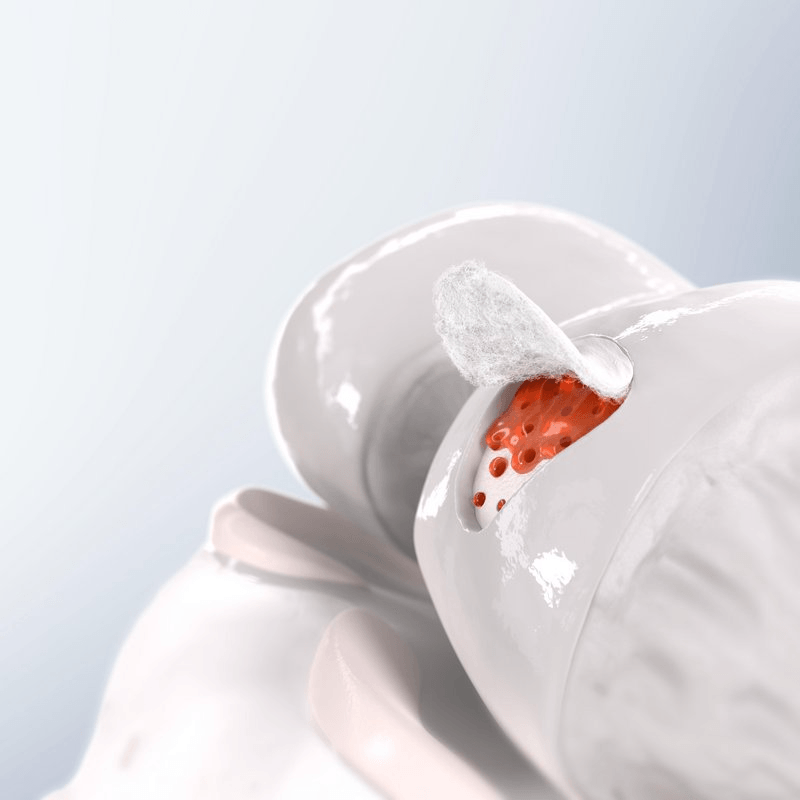

Dacă suprafața afectată este mai mică de 1cm2 se practică tehnica prin microfracturi. . Această tehnică se poate efectua într-o singură etapă. Pacientul nu se poate sprijini pe piciorul operat o perioadă de timp, perioadă determinată de localizarea condropatiei (leziunii de cartilaj).

- Tehnica chirurgicală de autoregenerare cu microfracturi Este o metodă prin care se practică niște găuri în osul rămas fără cartilaj până la stratul care conține celule ale măduvei hematogene. Sângele care vine din aceste găuri formează o rețea de fibrină care umple defectul condral în care vor migra în săptămânile următoare condrocite din cartilajul alăturat, sănătos. Astfel se formează un cartilaj cu calități inferioare față de cartilajul normal, dar cu rezultate clinice foarte bune atunci când suprafața defectului condral este sub 1 cm2